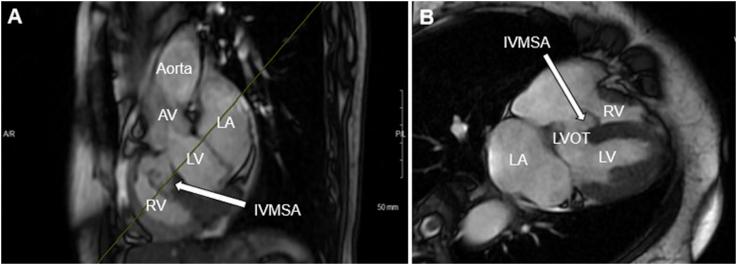

Multimodal Imaging Characterization of a Congenital Multilobular Interventricular Membranous Septal Aneurysm in a Patient Presenting with Embolic Stroke.

• TTE is often performed to search for cardiac sources of emboli. • TTE must be comprehensive and assess the atria, valves, and ventricles. • TTE can be utilized to identify IVMSA as a rare cause of recurrent strokes. • Comprehensive imaging studies should be utilized to confirm the diagnosis of IVMSA. • Multidisciplinary care is necessary in the management of these patients.